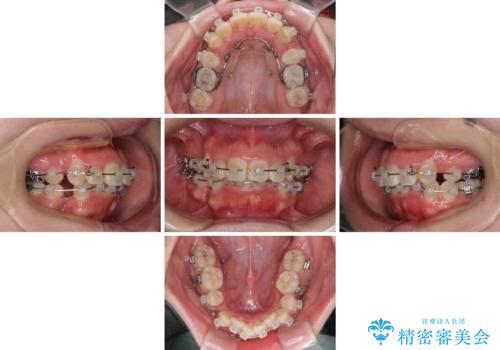

- 矯正装置

- クリアブラケット

- 治療計画

- 上下の八重歯やデコボコを気にして来院された患者様です。

上下ともに八重歯が顕著であったので、上下左右第一小臼歯4本を抜歯し、補助装置を使用して速やかに改善しながら、ワイヤー装置にて矯正治療を行うこととしました。

気になっていた八重歯は装置装着から3か月ほどで解消されました。

2年以内を目標として治療を開始しましたが、1年半ほどで終えることができました。